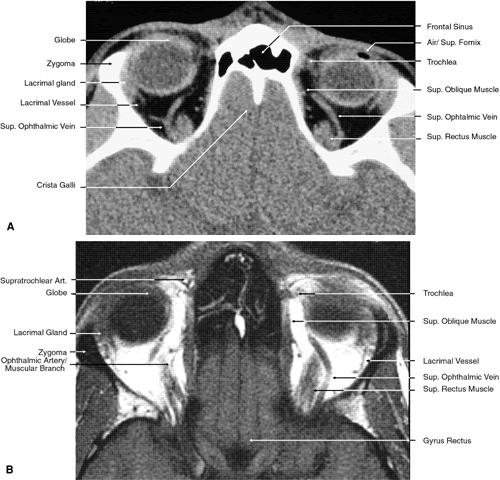

Fig. 17. Coronal images through anterior orbit. A. Computed tomography scan. B. T1-weighted magnetic resonance imaging.

Fig. 18. Coronal images through midglobe. A. Computed tomography scan. B. T1-weighted magnetic resonance imaging.

Fig. 19. Coronal images through midorbit posterior to the globe. A. Computed tomography scan.B. T1-weighted magnetic resonance imaging.

Fig. 20. Coronal images through orbital apex. A. Computed tomography scan. B. T1-weighted magnetic resonance imaging. C. Anatomic section of a cadaver head at the level of the orbital apex.

Fig. 21. Coronal images through optic canal. A. Computed tomography scan. B. T1-weighted magnetic resonance imaging.

Fig. 22. Axial images at the level of inferior orbit. A. Computed tomography scan. B. T1-weighted magnetic resonance imaging.

Fig. 23. Axial images at the level of midorbit. A. Computed tomography scan. B. T1-weighted magnetic resonance imaging.

Fig. 24. Axial images at the level of superior orbit. A. Computed tomography scan. B. T1-weighted magnetic resonance imaging.

Fig. 25. Axial images at the level of tendon of the superior oblique. A. Computed tomography scan. B. T1-weighted magnetic resonance imaging.

Fig. 26. T1-weighted magnetic resonance imaging; sagittal image through optic nerve.

The globe is shown in Figure 12. The orbit and periorbital structures are shown in Figures 13 through 16, and the optic canal is shown in Figures 17 through 26. The cavernous sinus and optic chiasm are shown in Figures 27 and 28, and the posterior visual pathway and cranial nerves are shown in Figures 29 through 33.